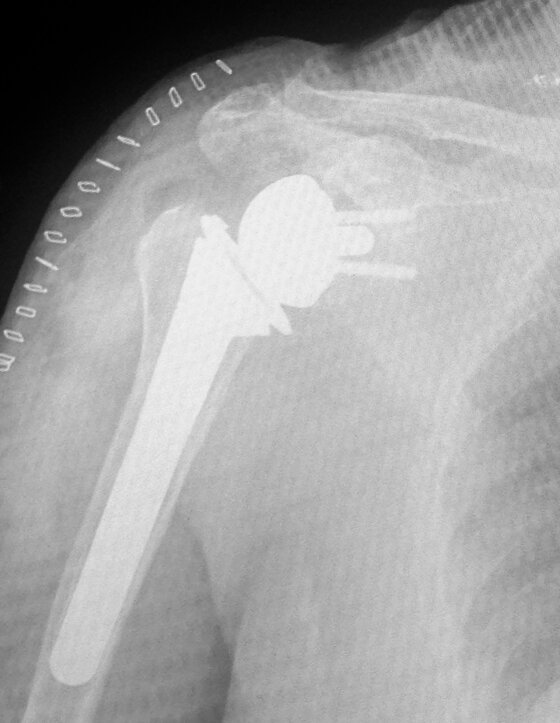

A sinistra radiografia post-operatoria di intervento chirurgico di protesi anatomica spalla effettuato in pz con necrosi testa omerale e cuffia dei rotatori integra.

Il trattamento nelle fasi iniziali si avvale di farmaci anti-infiammatori e terapia fisica per il controllo del dolore, riabilitazione per il mantenimento del tono muscolare e della mobilità articolare. Utili le infiltrazioni con acido ialuronico e la medicina rigenerativa (infiltrazioni o con PRP o cellule mesenchimali prelevate dal tessuto adiposo). Nelle fasi avanzate il trattamento indicato è l’intervento chirurgico di Protesi di spalla. Nell’ artrosi concentrica si utilizzano protesi o solo omerale o totale secondo lo stato della cavità glenoide. Nell’artrosi da rottura della cuffia si utililizza la Protesi Inversa che consente la mobilità attiva della spalla anche in assenza dei tendini della cuffia dei rotatori. Dopo la sostituzione protesica è necessario un intenso e prolungato percorso di fisiochinesiterapia.